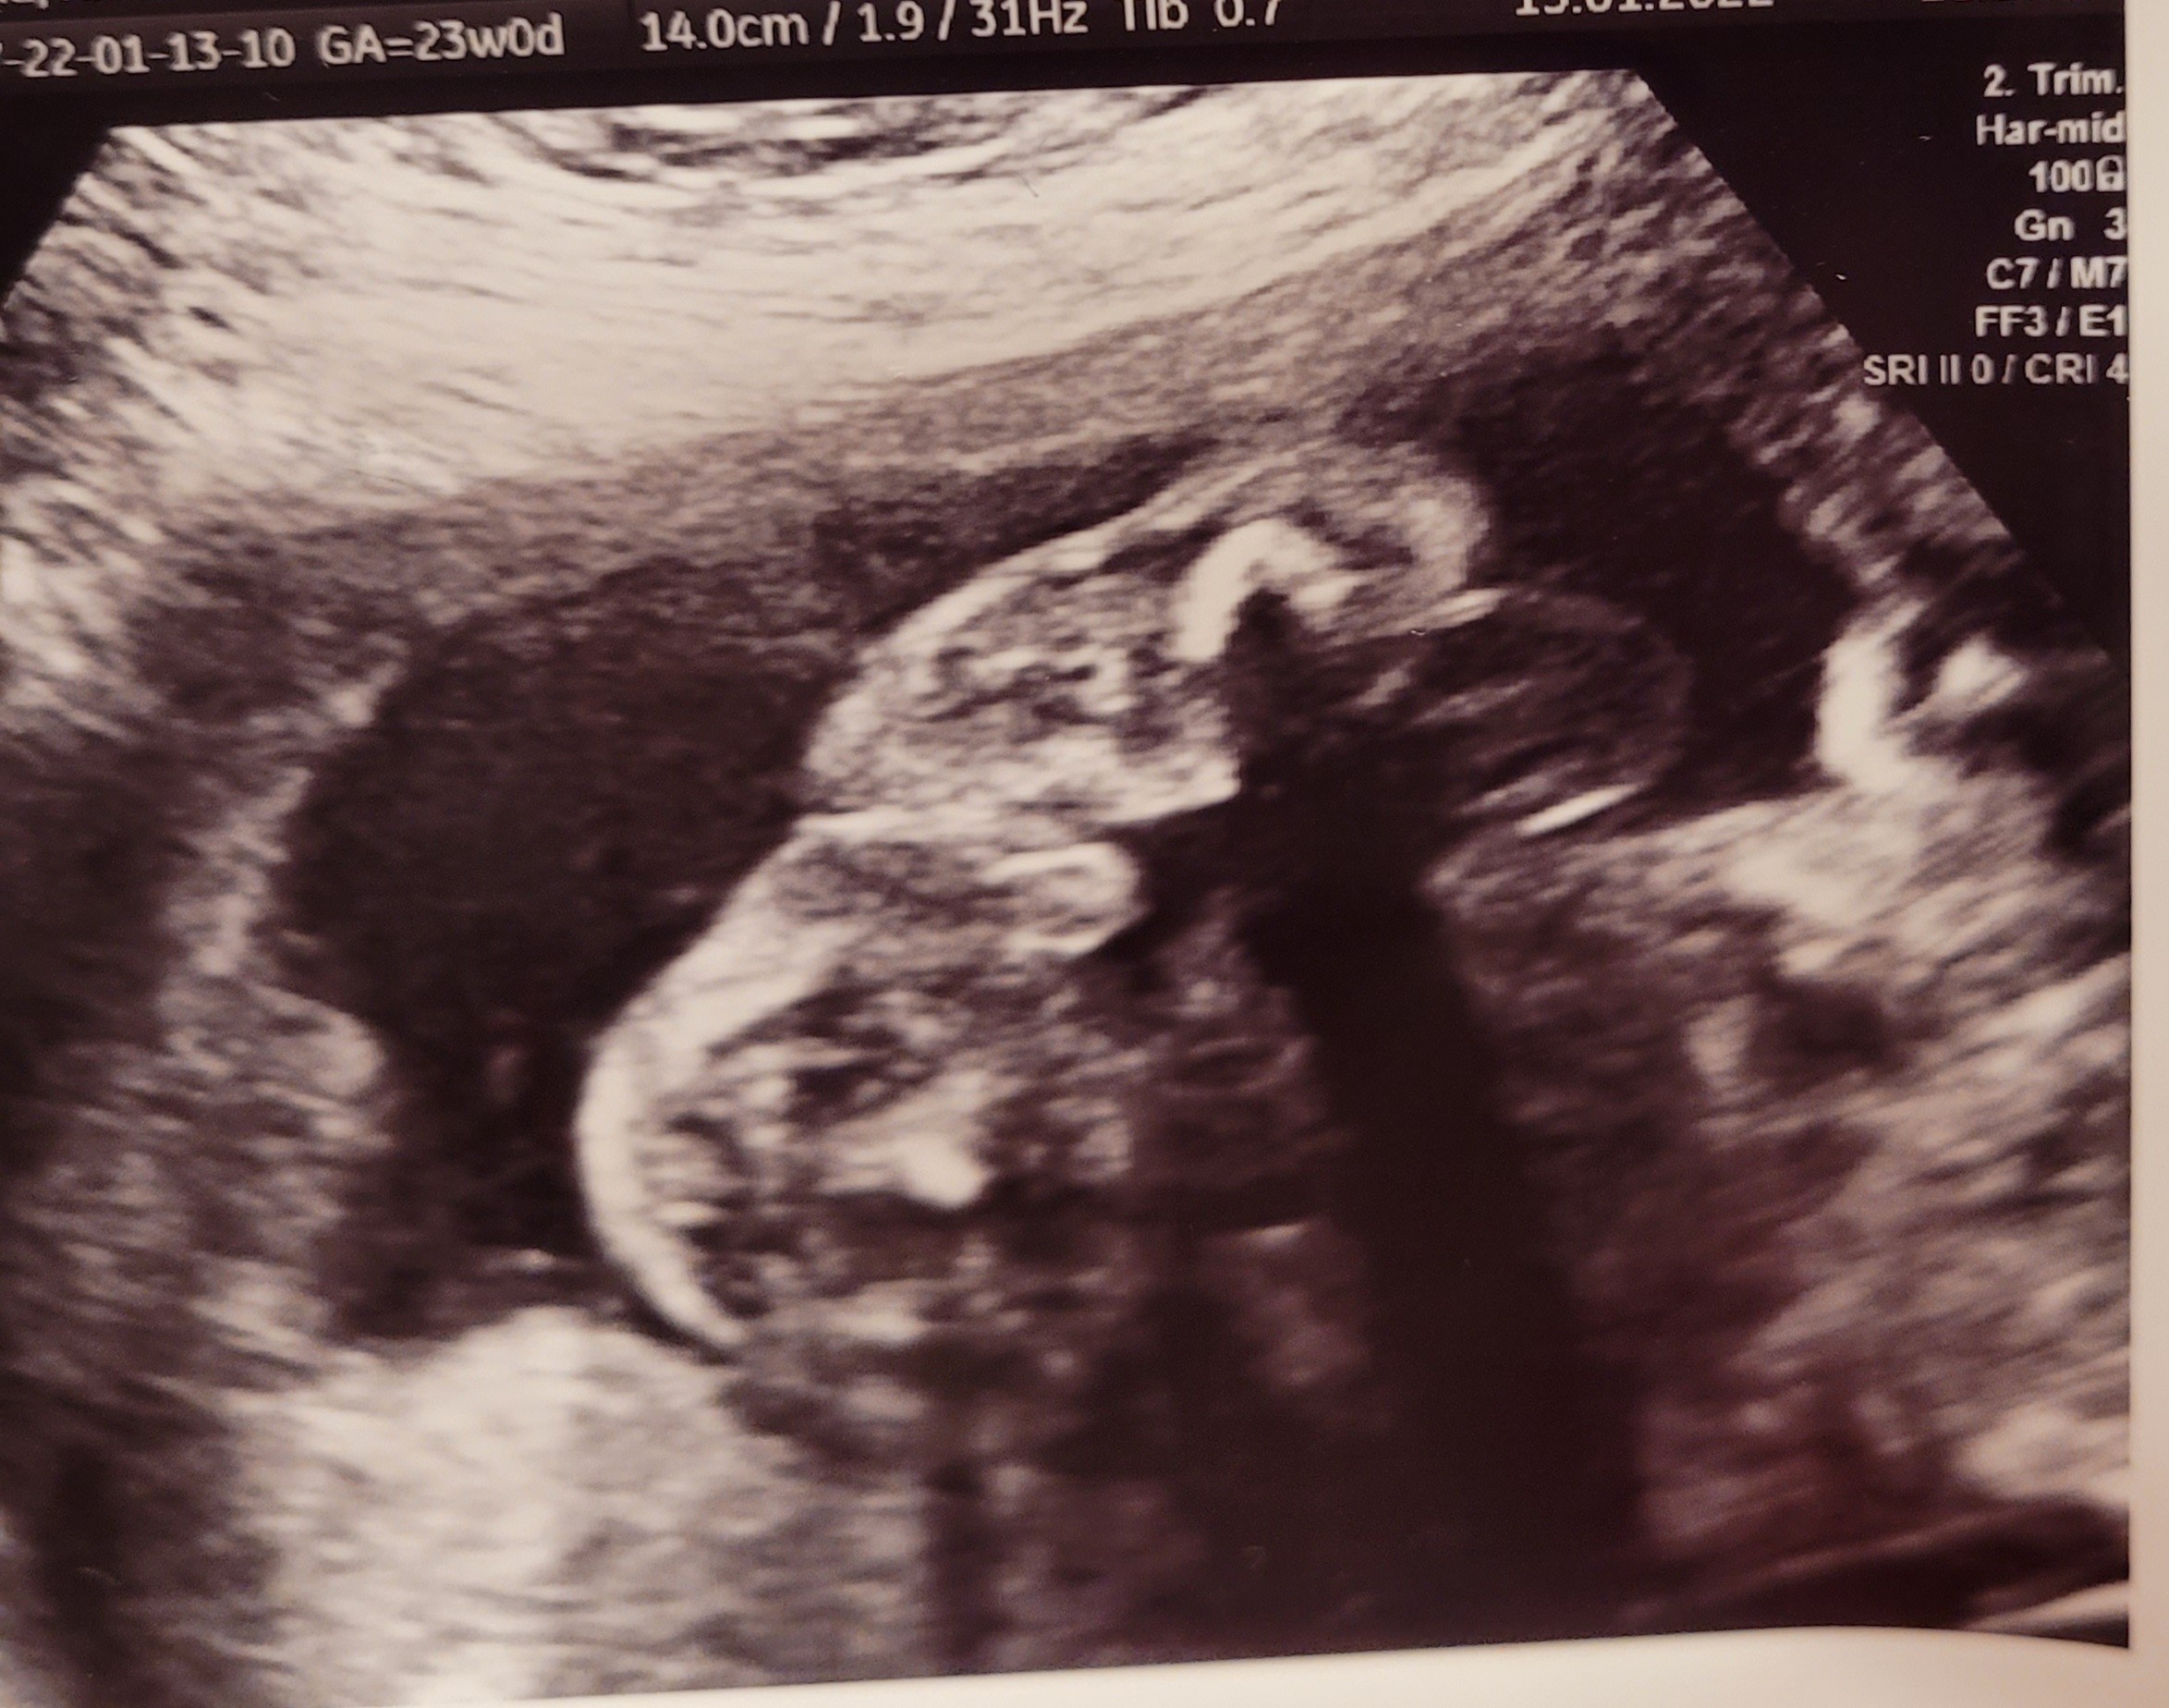

Płeć

Chlopiec czy dziewczynka?